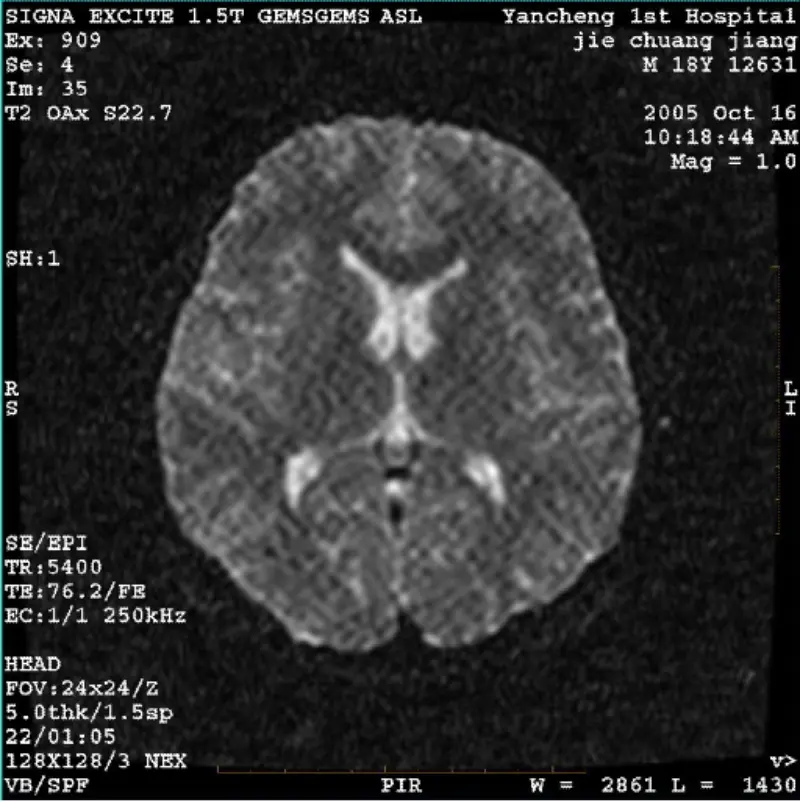

Читать далееСИСТЕМА: 1.5T Signa Twin Excite II (версия программного обеспечения 11.0M4) ПРОБЛЕМА/СИМПТОМ Изображение DWI (режим масштабирования и весь режим) и fiesta (режим масштабирования и весь режим) видимый сетчатый или вельветовый артефакт независимо от того, используете ли вы катушку для тела или го......